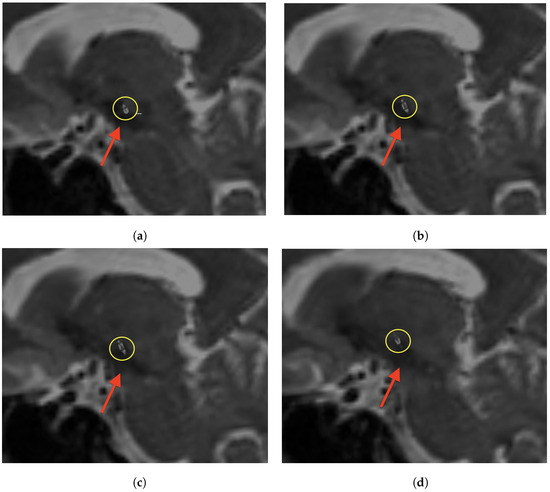

Figure 5.

Sagittal non-contrast T2-weighted MRI with DynaCT superimposed using alpha blending. The subthalamic nucleus is displayed as a T2-hypointense streak (red arrow). All parts of the electrode that are relevant for optimizing the stimulation can be clearly delineated (yellow circle). The image sequence transitions from medial (a) to lateral (d). (a) Proximal circular contact within STN. (b) Proximal segmented contacts for steering the electric field. (c) Distal segmented contact. (d) Distal circular contact.

Figure 6.

Axial non-contrast T2-weighted MRI with DynaCT superimposed using alpha blending. The subthalamic nucleus is displayed as a T2-hypointense streak (red arrow). All parts of the electrode that are relevant for optimizing the stimulation can be clearly delineated (yellow circle). The image sequence goes from caudal (a) to cranial (d). (a) Proximal circular contact within STN. (b) Proximal segmented contacts with blue stars indicating the segments for steering the electric field. (c) Distal segmented contact with blue stars indicating the segments for steering the electric field. (d) Distal circular contact.